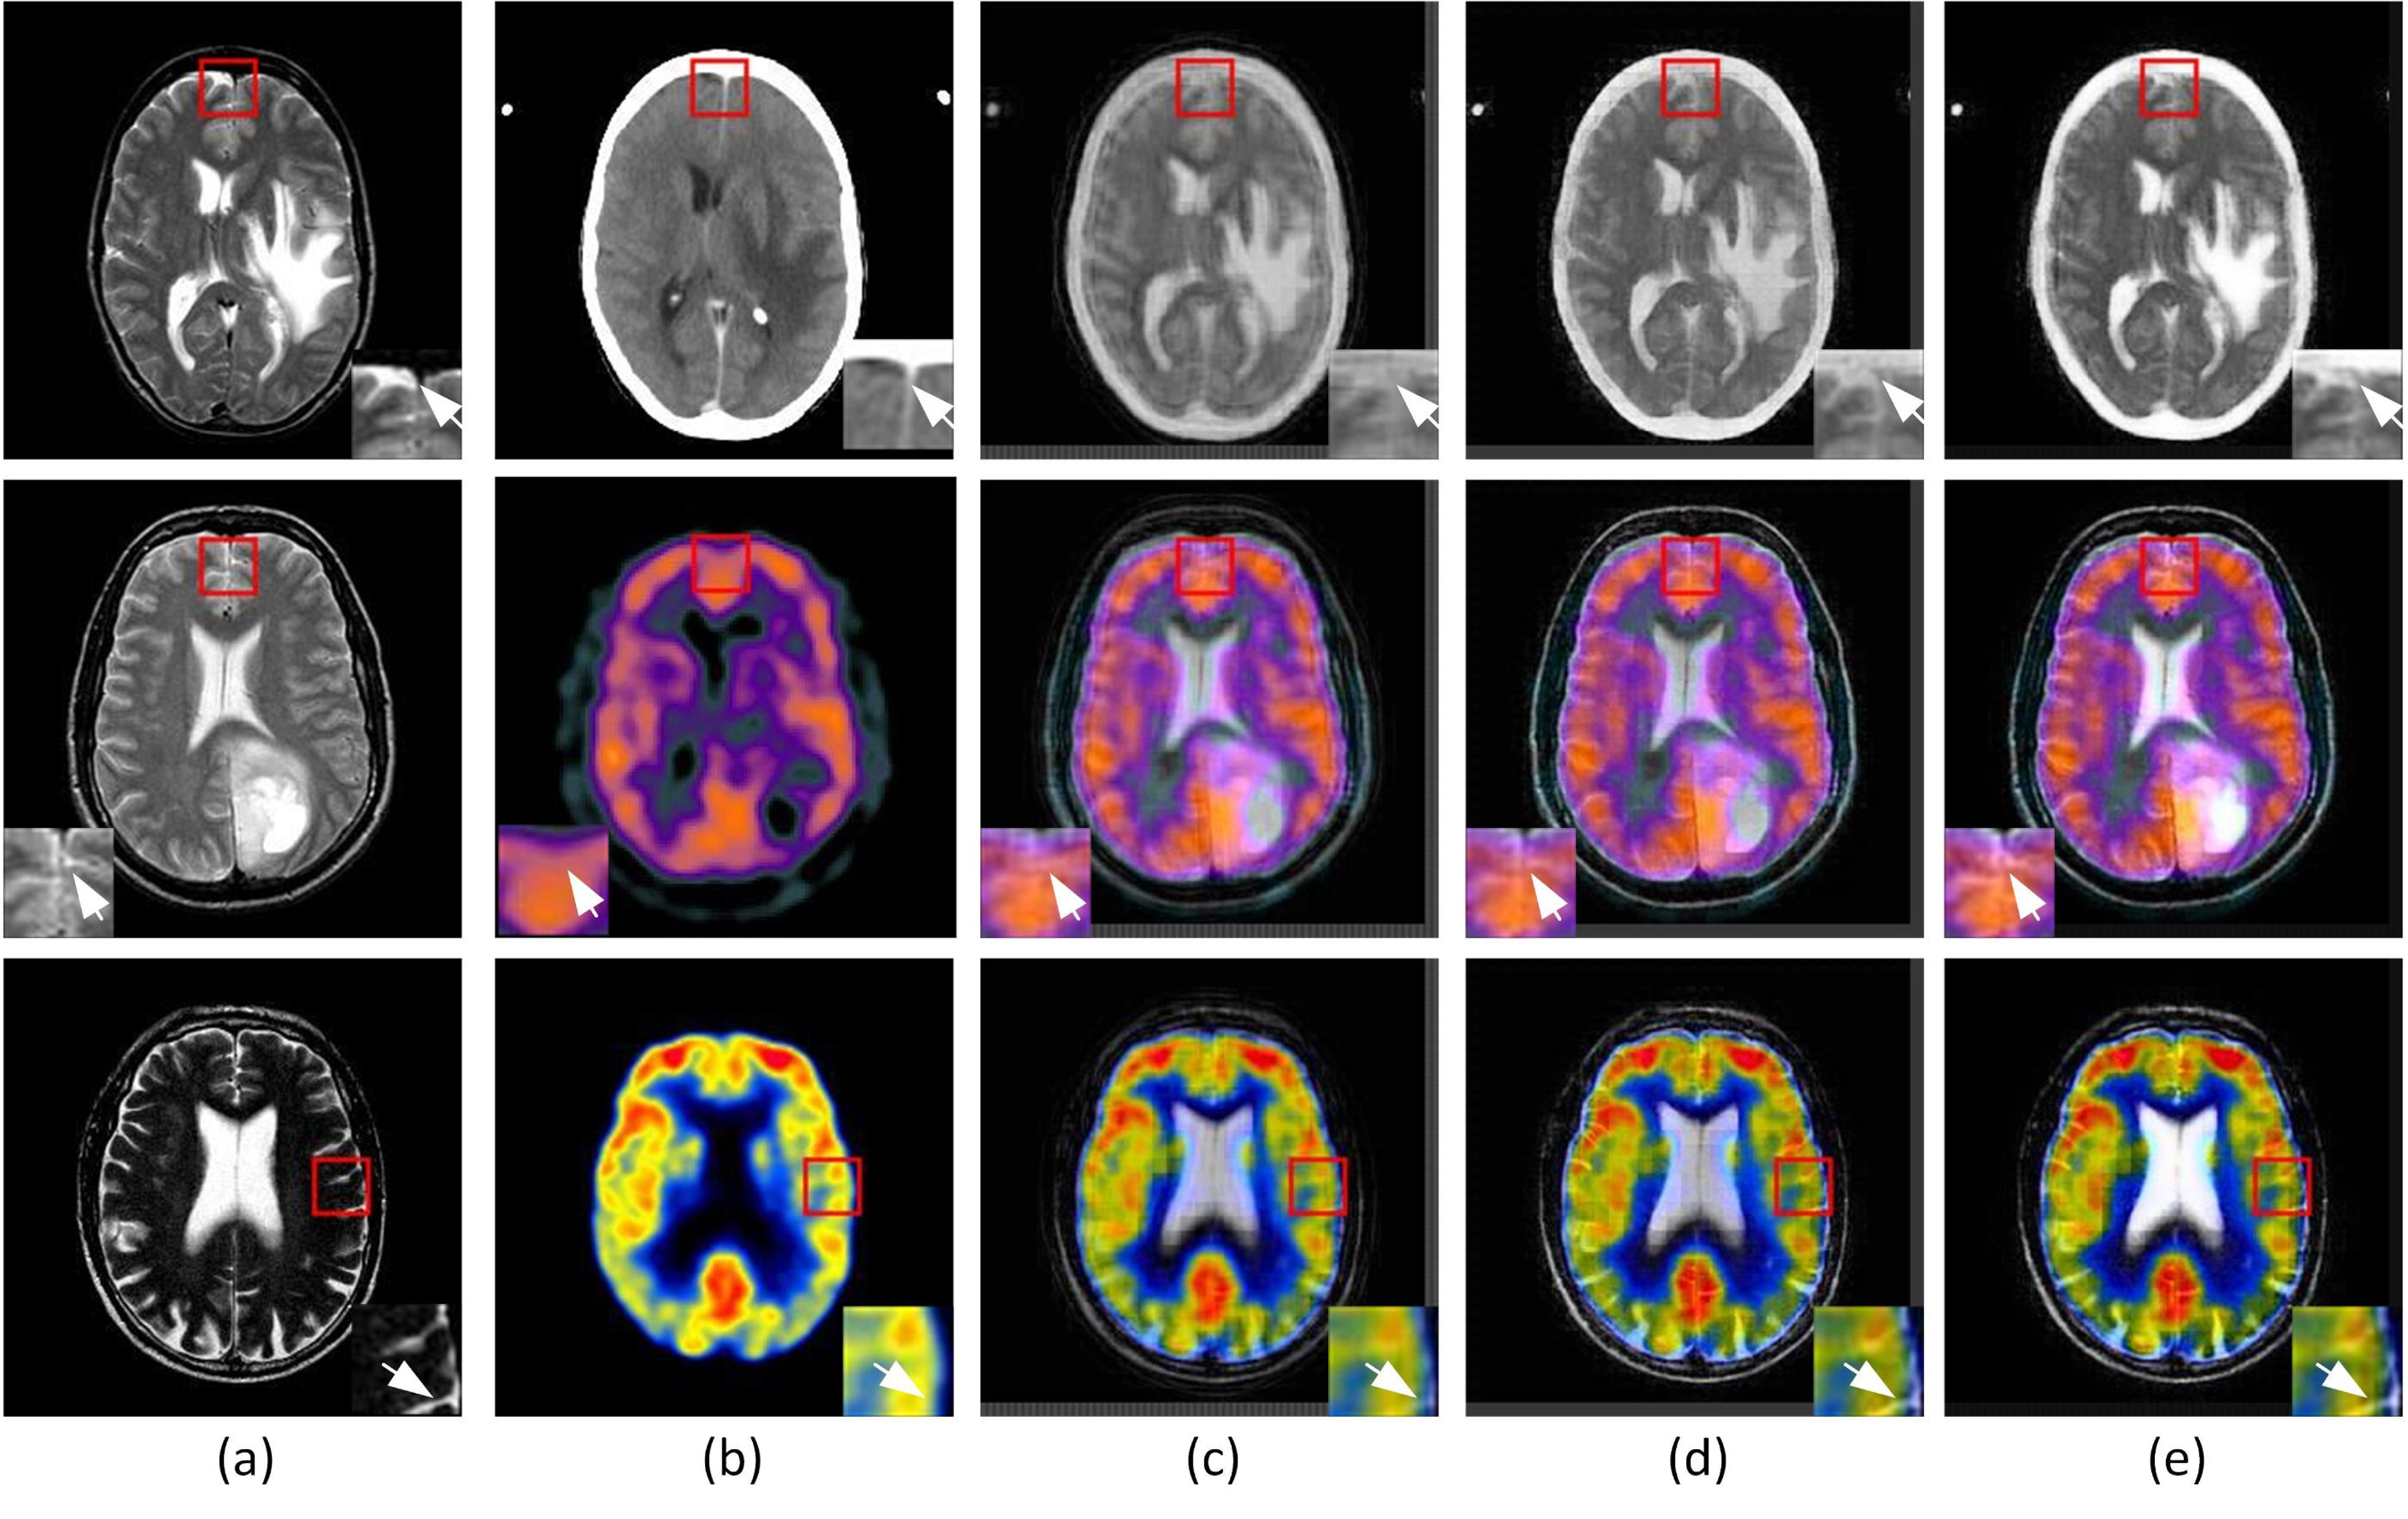

To explore the effectiveness of the LGCA pooling technique in enhancing the capability of the proposed fusion approach, an ablation study is conducted with the two most common techniques i.e. average and max pooling. The visual comparison is presented in Figure 6. Here, Figure 6 (a) and (b) display the source images and Figure 6 (c), (d), and (e) display the fusion results obtained by employing the average, max, and LGCA pooling techniques, respectively, in the CAE architecture used in the proposed fusion method. The rest of the blocks of the CAE, dataset, hyperparameters, and implementation platform are kept the same. Figure 6 shows specific zoomed regions of the fused images for better visualization of the results obtained using each pooling technique.

Refer to caption

Figure 6: Subjective Comparison of fusion results with three pooling methods (a) Input Image 1 (MR T2 Image), (b) Input Image 2 (CT/SPECT/PET Image), (c) Average pooling, (d) Max pooling, (e) LGCA pooling.

It can be observed from Figure 6 that the fusion results of each pooling technique capture the structural information accurately but for the average pooling in Figure 6 (c), the fused images are of very low resolution with muted edges and blurred spatial details of the input images. Efficient preservation of the edge information with vivid contrast is observed in the fusion results of the LGCA pooling. For MR T2-CT fusion, compared to the max pool fused image, both soft and hard tissue demarcations with strong contrast are produced in the fusion result of LGCA pooling. For MR T2-SPECT and MR T2-PET fusion, compared to the max pool, LGCA pooling fusion results are of richer color consistency and finer local as well as global contrast. The soft tissue delineation along the skull’s inner boundary in MR images is also more prominent in the resultant fused images with the LGCA pooling method. Compared to the fusion results of the other pooling techniques, the complementary information is preserved to a greater extent by the LGCA pooling.

The quantitative performance analysis for Figure 6 is presented in TABLE IV. In TABLE IV, for each image pair, the LGCA pooling achieves the highest values for performance measures SD, QAB/Fsubscript𝑄𝐴𝐵𝐹Q_{AB/F}, QCsubscript𝑄𝐶Q_{C}, QYsubscript𝑄𝑌Q_{Y} and SCD which further supports the visual evaluation of the fusion results. Overall for EN metric, Max-pool shows significant performance but LGCA-pooling gains notable results for MI values. Discussing the visual clarity in fusion outcomes, LGCA-pool has an overall marked increment in SF measure. The proposed fusion method achieves top performance for visual information metric VIFF, in case of CT-MR fusion, and comes in second to max-pool for the fusion of anatomical-functional pairs 2 and 3 in TABLE IV.

The averaged quantitative analysis for the three pooling techniques is presented in TABLE V. It is observed that the proposed method has significantly better results for metrics SD, SF, QAB/Fsubscript𝑄𝐴𝐵𝐹Q_{AB/F}, MI, QCsubscript𝑄𝐶Q_{C}, QYsubscript𝑄𝑌Q_{Y} and SCD. The following observations are drawn,